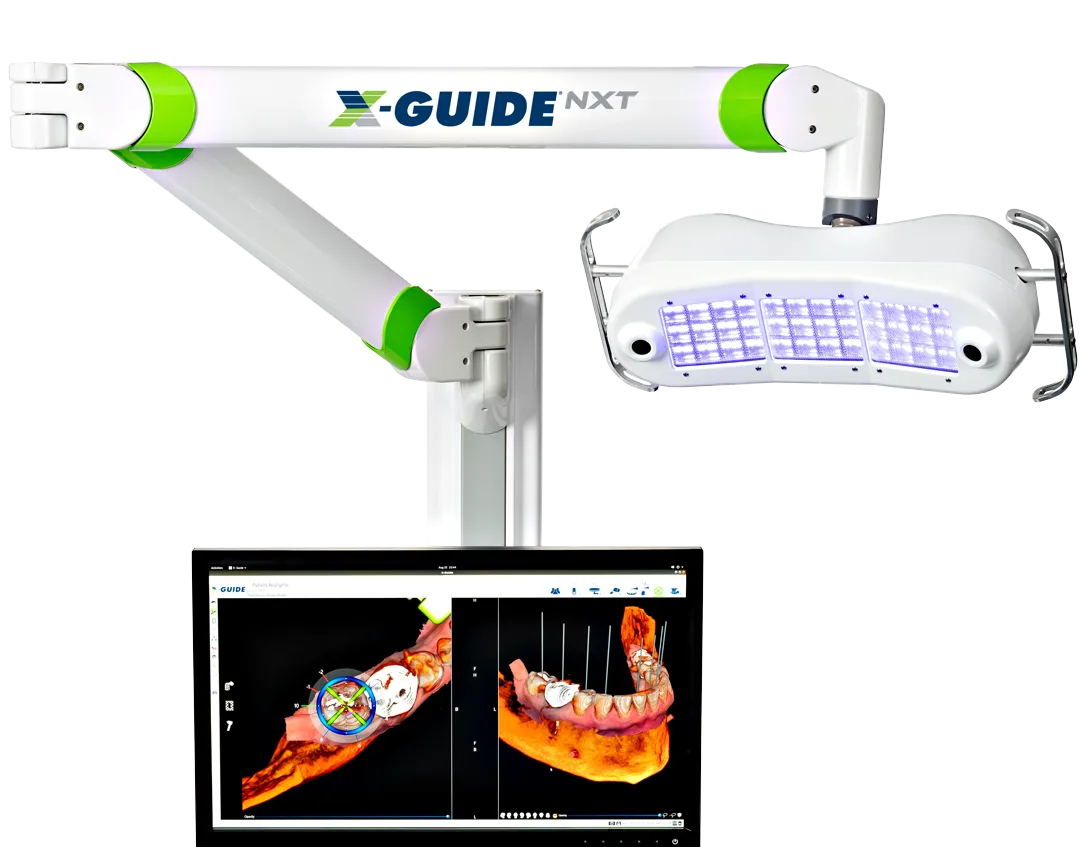

Dynamic 3D Navigation for Implant Precision

Now featuring PrecisionArch™ — a guided, flapless system for safer, more precise implant placement.

At Modern Day Smiles, we bring digital planning to life in real time, so you get safer, more precise implant placement.

Thanks to Dynamic 3D Navigation technology, we can control the exact position, angle, and depth of your implant with pinpoint accuracy. This system has been shown to be significantly more accurate than traditional freehand surgery, giving you a higher level of safety and predictability.

This level of precision means fewer incisions, less discomfort, and a faster healing experience, helping you get back to normal life sooner.

It’s an advanced approach that allows us to deliver safe, predictable, natural-looking results, all in a single visit.

Dynamic Navigation 11X more accurate than freehand implant surgery.

A Perfect Smile With 3D Digital Imaging

PrecisionArch™ Gives You Greater Precision, Faster Surgery, Faster Recovery!

By using the latest 3D digital imaging technology and a fully digital workflow, we can plan and place your implants with far greater precision, so you get safer, more predictable results.

This advanced scanner captures detailed images of your teeth, gums, bone, and facial structure. With this information, we’re able to design a treatment plan that fits you perfectly and ensures your implants are positioned exactly where they need to be.

This way, your smile will be exactly how it was meant to look.

Many dentists only use a CBCT scanner, but not many use this new technology. We are the ONLY team of Periodontists, Prosthodontist, Oral Surgeons and General Dentists in the Tampa Bay area using Photogrammetry technology.